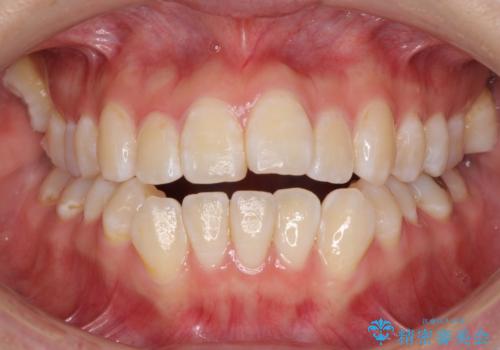

外に飛び出して磨きにくい奥歯と上下前歯の隙間 インビザラインによる矯正治療

- 上下前歯の隙間と、外側を向いていて歯磨きのしにくい奥歯を気にして来院された患者様です。

下顎前歯が1本欠損しており、上下アーチはアンバランスとなりますが、インビザラインを用いて上下の隙間を改善しながら歯列を整えることとしました。